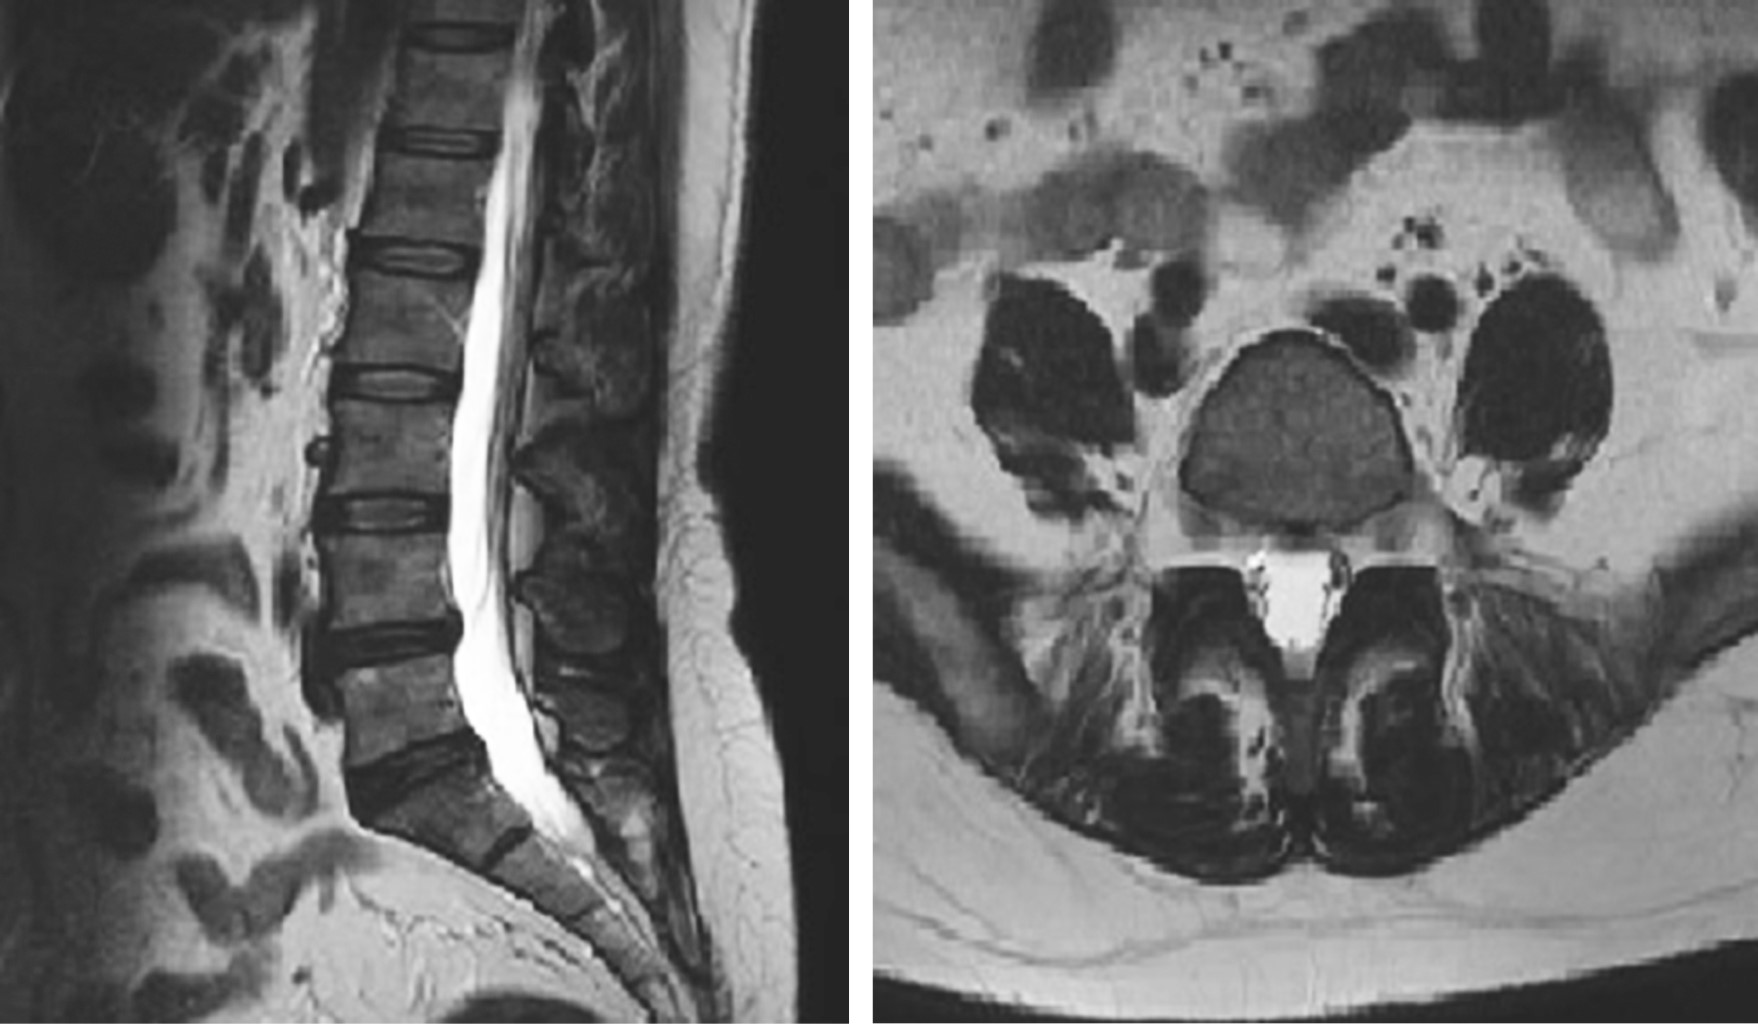

Técnica quirúrgica: abordaje posterior de 10 cm, desde el trocánter mayor hacia la espina iliaca posterosuperior, se visualiza el tendón piramidal, se suturó la porción tendinosa y se realizó tenotomía del tendón, se diseca cuidadosamente hasta localizar el nervio ciático, el músculo es llevado hacia el extremo proximal de la escotadura ciática mayor. Se moviliza el nervio ciático desde los músculos rotadores y piramidal a través de una disección roma distalmente y proximalmente al agujero ciático mayor. Era posible pasar una pinza en ángulo recto entre los músculos rotadores y el nervio después de la liberación del nervio (Figura 4). Tiempo de cirugía: 60 minutos, sangrado < 60 minutos.

Figura 4